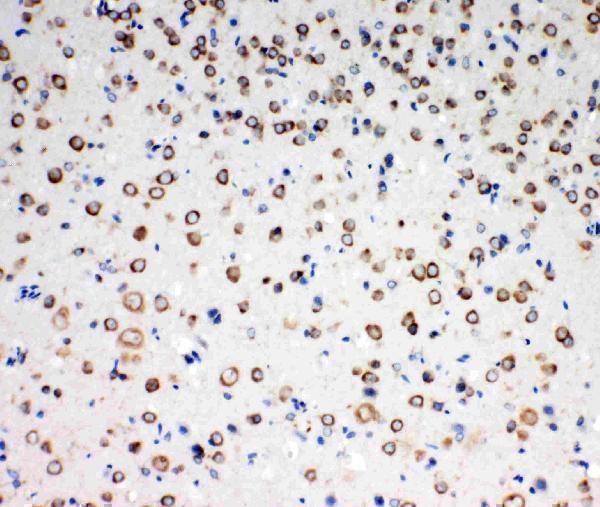

Facts about NT-3 growth factor receptor.

| Gene Name: | NTRK3 |

| protein kinase superfamily |

Widely expressed but mainly in nervous tissue. Isoform 2 is expressed at higher levels in adult brain than in fetal brain.

Membrane; Single-pass type I membrane protein.